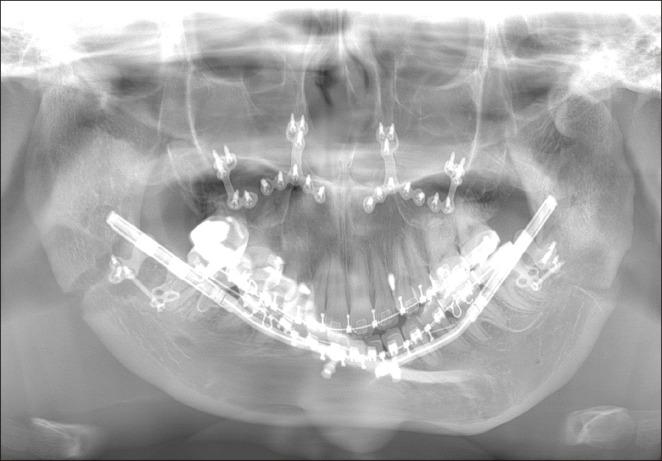

Untreated mandibular condyle fractures in childhood can result in significant jaw deformities, such as mandibular retrognathism, open bite, and facial asymmetry, which may necessitate surgical intervention in later years. Surgical approaches vary depending on the severity of the condition, including mandibular surgery alone, maxillomandibular surgery, or mandibular distraction osteogenesis (MDO). This report highlights a case involving mandibular retrognathism and open bite with condylar dislocation and malunion caused by untreated pediatric condyle fractures. Key challenges in this case included excessive anterior mandibular movement, irregular morphology of the mandibular ramus caused by malunion from fracture healing, and anteromedial dislocation of both condyles, all of which posed significant surgical complexities. The surgical approach combined Le Fort I osteotomy with MDO to perform maxillary impaction and mandibular advancement, followed by a secondary genioplasty. Notably, the dislocated temporomandibular joints were left untreated. Two years postoperatively, no relapse or recurrence of open bite was observed, and the dislocated condyles showed no positional and morphological changes, reflecting favorable outcomes. To our knowledge, this is the first reported case of orthognathic surgery combined with MDO for bilateral dislocated mandibular condyles, making it a valuable contribution to clinical practice.

儿童期未经治疗的下颌髁突骨折可导致严重的颌骨畸形,如下颌后缩、开颌和面部不对称,这可能在日后需要手术干预。手术方法因病情严重程度而异,包括单纯下颌手术、上颌下颌联合手术或下颌骨牵张成骨术(MDO)。本报告重点介绍了一例因儿童期髁突骨折未经治疗导致下颌后缩、开颌伴髁突脱位和骨不连的病例。该病例的主要挑战包括下颌前部过度移动、骨折愈合导致的骨不连引起的下颌升支形态不规则以及双侧髁突向前内侧脱位,所有这些都带来了重大的手术复杂性。手术方法结合了Le Fort I截骨术和MDO,以进行上颌骨上移和下颌骨前徙,随后进行二期颏成形术。值得注意的是,脱位的颞下颌关节未进行治疗。术后两年,未观察到开颌复发或再发,脱位的髁突也未出现位置和形态变化,显示出良好的效果。据我们所知,这是首例报道的正颌手术联合MDO治疗双侧脱位下颌髁突的病例,对临床实践具有重要价值。